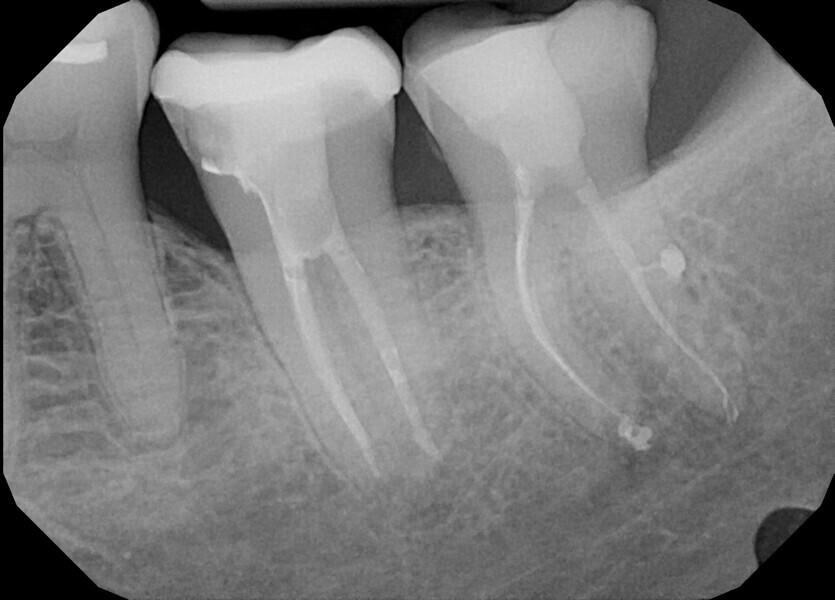

A 40-year-old female patient was referred to Dr Karaś’s office because tooth #47 was symptomatic and tender to percussion. During examination with a conventional radiograph, the referring dentist could not find any visible signs of the root canals, so he would not have been able to shape the root canals properly.

During the consultation appointment, a CBCT scan was performed. It revealed a small osteolytic lesion around the mesial root, suggesting the possibility of achieving patency in the root canals in the mesial root. Around the distal root, there were no signs of the lesion, which indicated that the mesial root was the cause of the symptoms. The radiographic examination also revealed a broken lentulo in the MB canal (Fig. 16).

Figs. 16 a & b